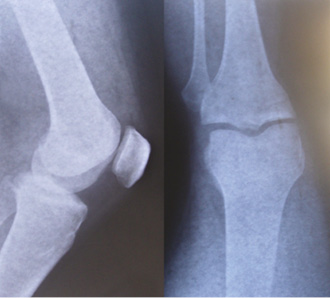

Feel the bones in your forearm, upper arm, lower leg and upper leg. Try to find the number of bones in each part. Similarly, feel the bones of your ankle and knee joints and compare these with the X-ray images (Fig. 8.8).

Fig 8.8 X-ray images of ankle and knee joints